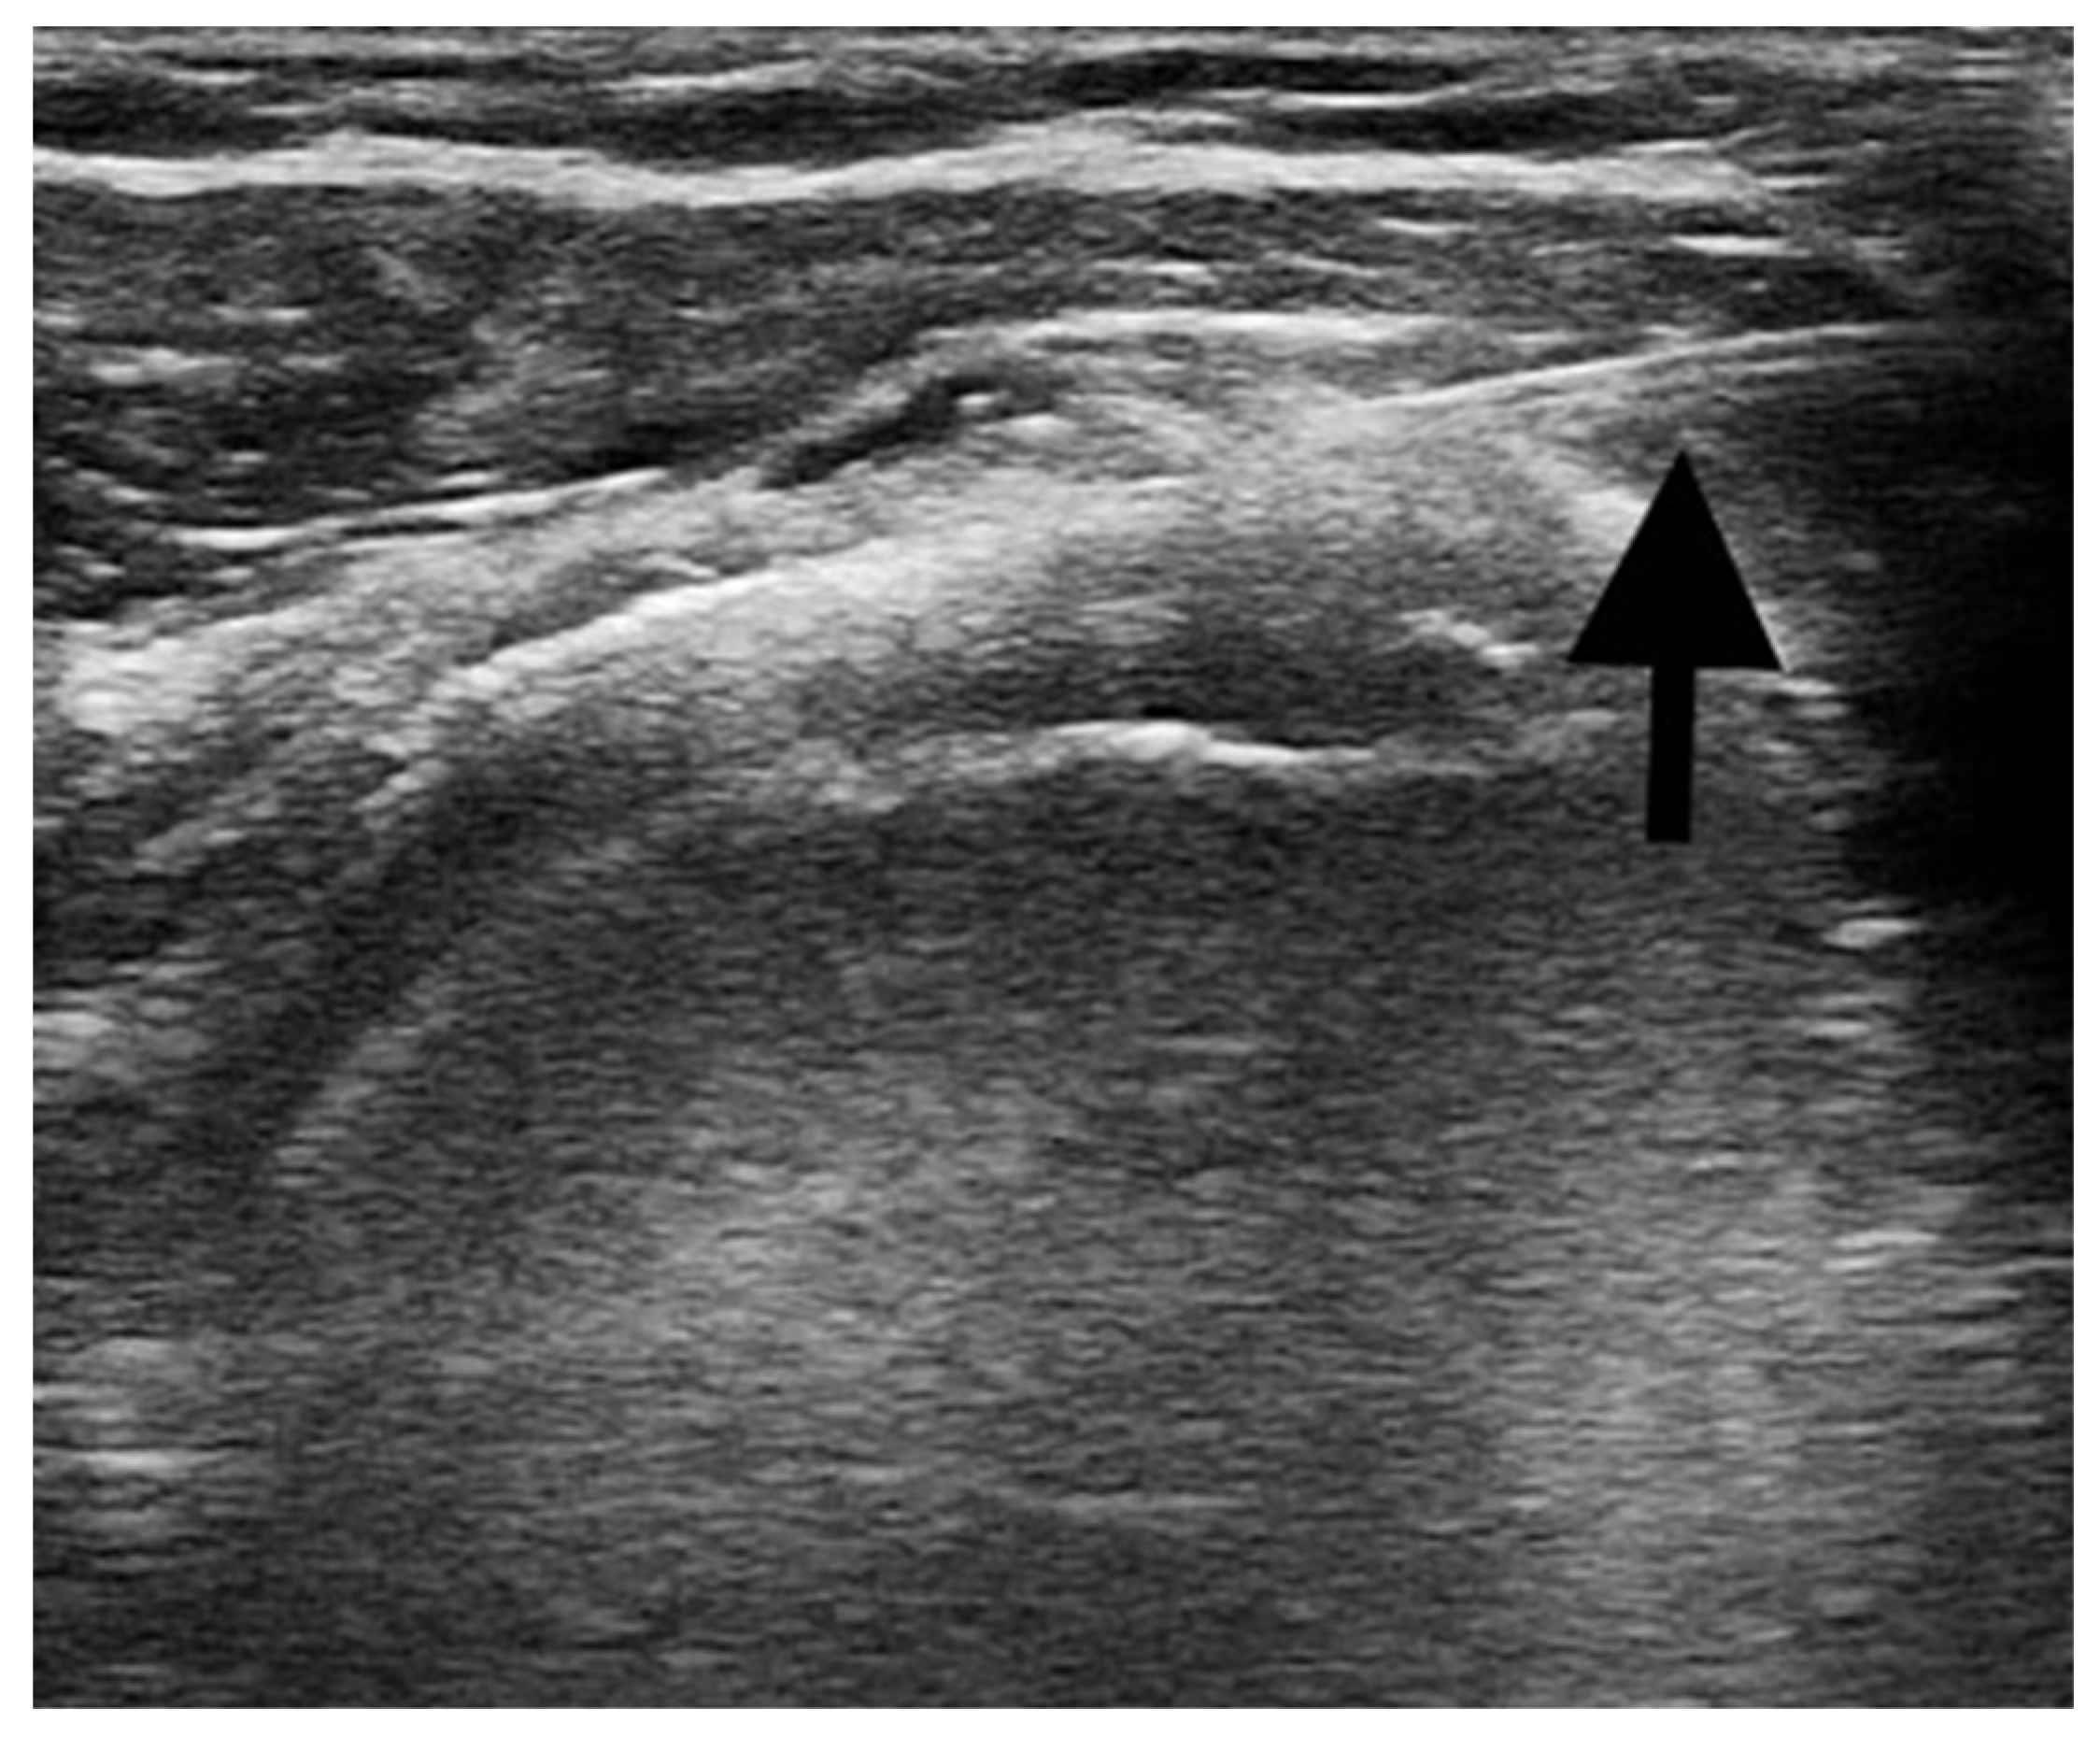

Ultrasound-guided injections: the procedures were performed with the patient supine and positioned with the shoulder adducted and slightly extra rotated, the upper limb laying along the side. A US machine (Mindray® M7 Bio-Medical Electronics Co, Ltd., Shenzhen, China) with a linear transducer (8–12 MHz) was used to identify the subacromial bursa and to guide the injection procedure. After the preparation of the sterile field, a US-guided percutaneous injection of 1 mL of 40 mg triamcinolone acetonide combined with 3 mL of 1% lidocaine was performed in the affected subacromial bursa [31,32]. A 22-gauge needle was used and the correct positioning of the needle directly into the bursa was real-time confirmed under US guidance. Figure 1 shows the US image of the percutaneous injection procedure.

Figure 1. The figure shows the correct positioning of the needle (black arrow) inside the sub-acromion deltoid bursa during the ultrasound-guided injections procedure.